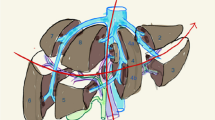

Maximum dose delivered to the heart (mean 25.3 Gy vs. 24.5 Gy, p = 0.048) and ribs (mean 38.7 Gy vs. 37.7 Gy, p = 0.044) was significantly higher for simple IMRT (figure 3) but no other statistically significant differences were seen in other OARs, liver Veff, biological liver NTCP or mean liver dose. Examples of simple IMRT and index IMRT plans are shown in figure 4.

Axial (left panels) and Coronal (right panels) slices of acceptable index and simple IMRT, showing the six fraction, lowest isodose covering 0.5 cc PTV (orange), the 30 Gy isodose (dark blue) and 10 Gy isodose (beige) surrounding the PTV (pink colorwash). Examples are shown of a small lesion typical of liver SBRT (A), where loss of dose conformation of higher isodoses may have larger effects on normal tissue function, as compared to a larger lesion near bowel treated to lower doses (B).